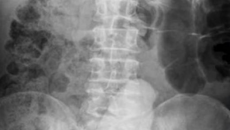

68-годишен отива на лекар с болки в кръста и корема, вижте какво намерили лекарите

68-годишен мъж отишъл на лекар с болки в кръста и корема,  а лекарите останали с отворени уста, след като направили рентгенова снимка. Странната находка в седалището на 68-годишен мъж се оказал вибратор, дълъг 23 сантиметра. Той бил проникн...